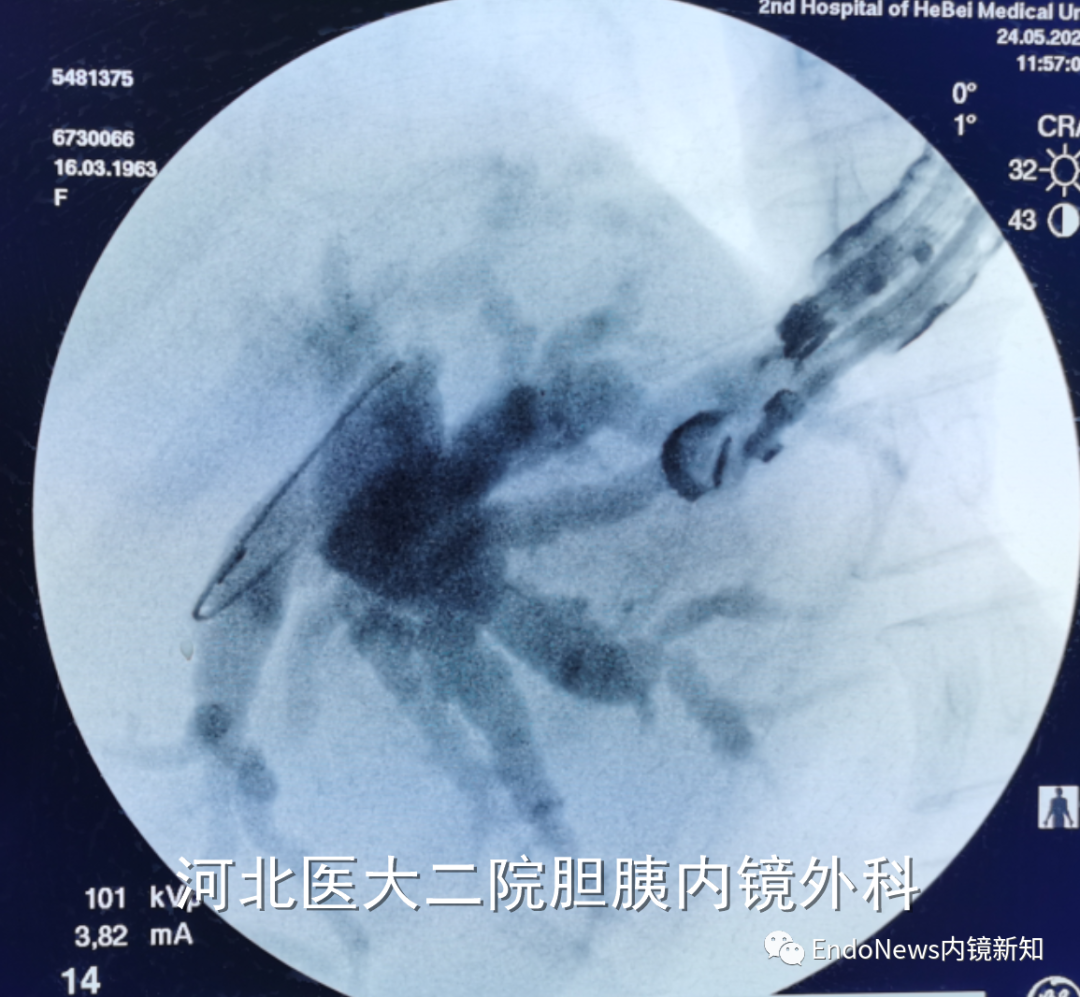

行经十二指肠胆管穿刺(CDS)时一般不需要考虑以上问题,但如因某些特殊原因涉及到会师操作时可能涉及到导丝自胆总管上游朝向下游的超选。一般情况下,CDS的时候穿刺针的方向是朝向肝内的,比如下图:

如果这个时候放支架行CDS就可以结束手术了,如果需要做顺行或者会师,就需要使导丝返折180°朝向胆管下游方向穿出十二指肠乳头。